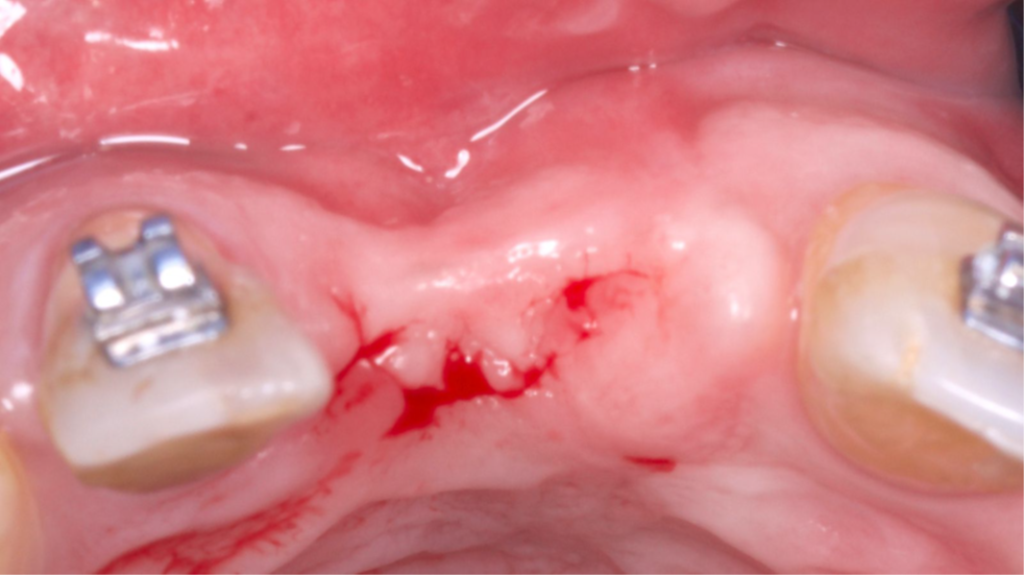

Paciente do sexo masculino encaminhado pela Ortodontia para a instalação de um implante ao nível do dente 1.1 (Figura 1), com diastemas mésio-distais de 2mm, para utilização do implante como ancoragem absoluta e melhor andamento da movimentação ortodôntica.